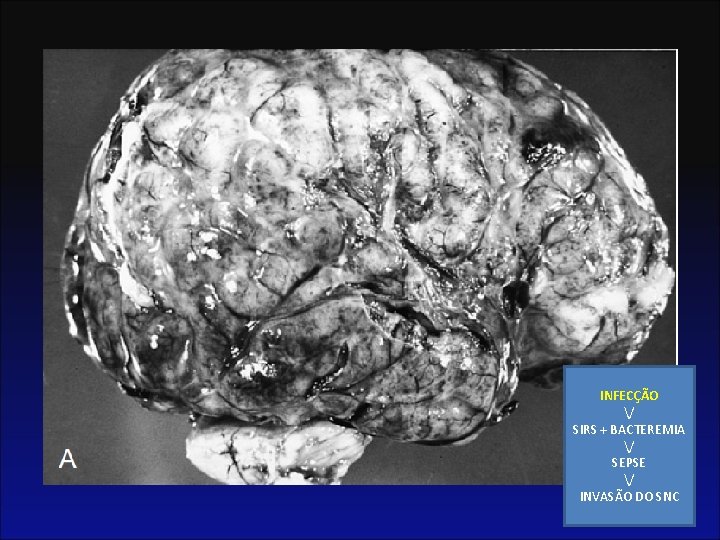

Protocolo • Objetivo: não chegar neste ponto:

FISIOPATOLOGIA INFECÇÃO / SIRS + BACTEREMIA / SEPSE / INVASÃO DO SNC

Fisiopatologia • No estado agudo (primeira semana) – Exsudado: leucócitos polimorfonucleares. – Bactérias visíveis, livre e dentro de leucócitos polimorfonucleares e macrófagos – O exsudato inflamatório é particularmente proeminente em torno de vasos sanguíneos. • Segunda e terceira semanas – Polimorfonucleares mononucleares (histocitos e macrófagos)

Infecções Bacterianas • 73 -88% Ventriculite • 30 a 50% Infarto • 15% Abscessos cerebrais INFECÇÃO / SIRS + BACTEREMIA / SEPSE / INVASÃO DO SNC